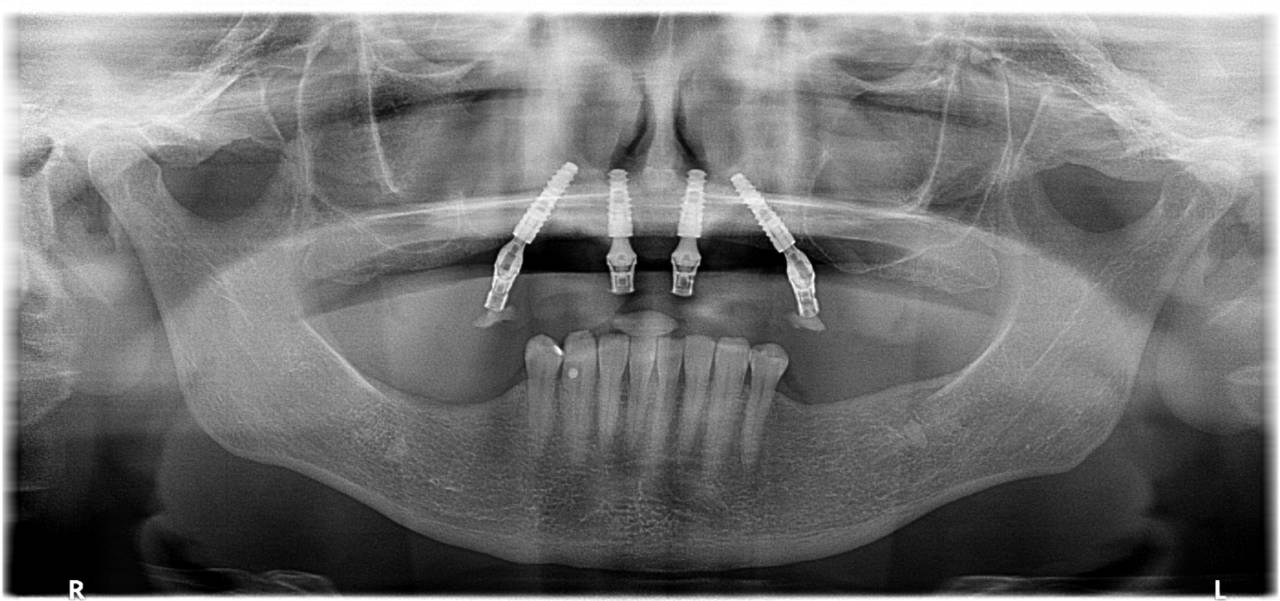

O Protocolo All On 4 é uma técnica revolucionária para reabilitação oral total em pacientes que perderam todos os dentes ou que possuem dentição severamente comprometida. Na Medeiros Odontologia, em Colatina, somos especialistas no Protocolo All On 4, oferecendo uma solução fixa e duradoura, que devolve a estética e a função do sorriso em uma única cirurgia. Essa técnica utiliza apenas quatro implantes para sustentar uma prótese completa, garantindo um resultado estável e natural.

• Material: Implantes de titânio biocompatíveis que servem como base para a fixação de uma prótese total, substituindo todos os dentes superiores ou inferiores.

• Procedimento: Em uma única cirurgia, são instalados quatro implantes estrategicamente posicionados, permitindo a colocação imediata de uma prótese fixa. A recuperação é rápida e o paciente sai da clínica com dentes novos no mesmo dia.